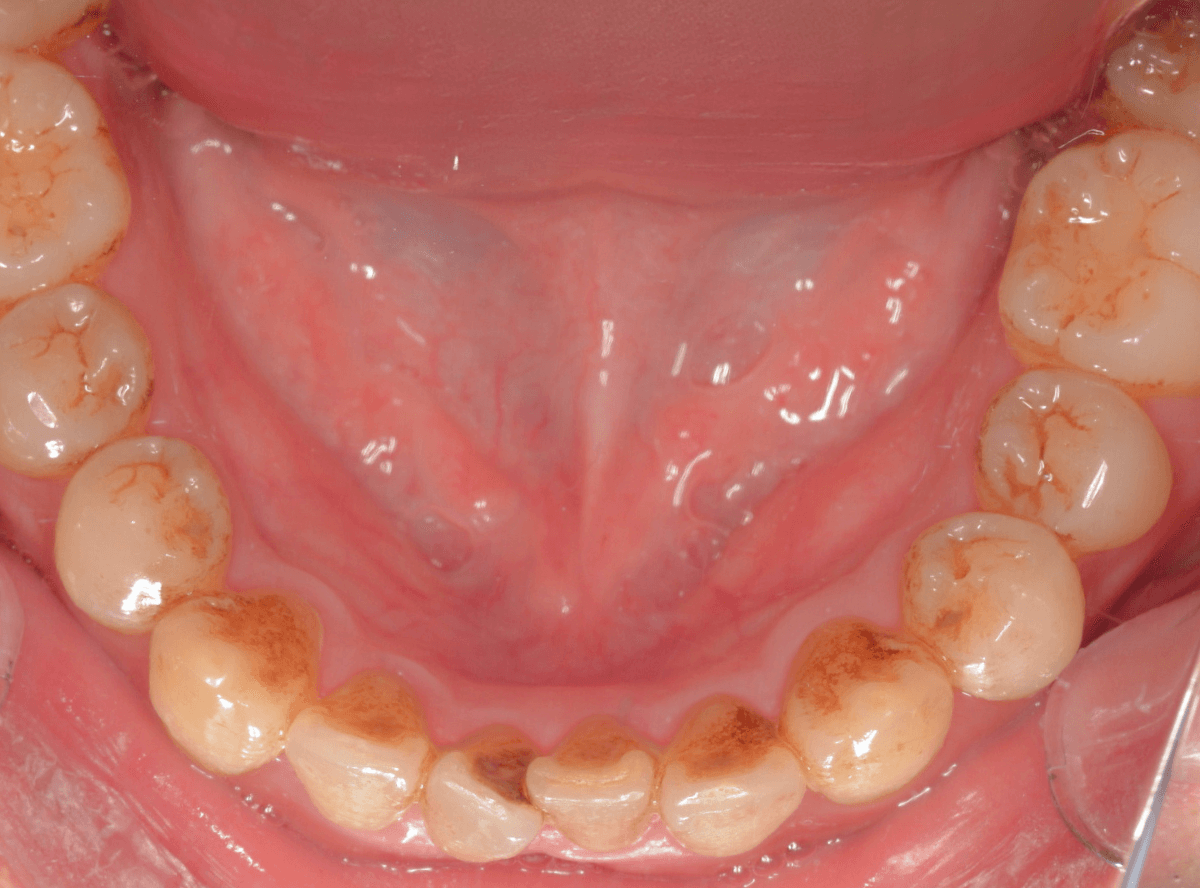

ビューティークリーニング後の状況です。

通常の歯石除去時には落としきれない、歯の裏側の着色まで専用器具をつかって、時間をかけてしっかり除去します。

特に汚れの多かった下の前歯の裏側を比較すると、より変化がわかりやすいかと思います。